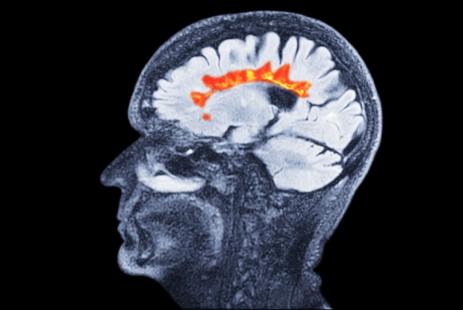

Vumerity est un nouveau médicament du Laboratoire Biogen indiqué dans la sclérose en plaques rémittente récurrente (SEP-RR), qui renferme un nouveau principe actif, le diroximel fumarate.

Vumerity 231 mg, en gélules gastrorésistantes, est un nouveau médicament indiqué dans la sclérose en plaques de forme rémittente récurrente (SEP-RR). Il contient un nouveau principe actif, le diroximel fumarate, un immunosuppresseur similaire au diméthyle fumarate, principe actif de Tecfidera (Laboratoire Biogen). En effet, le diroximel fumarate (DRF) et le diméthyle fumarate (DMF) sont convertis dans l'organisme sous le même métabolite actif principal, le monométhyl fumarate.